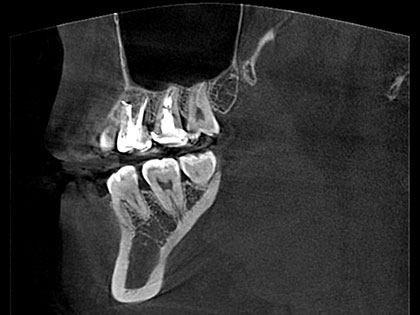

• 術前の写真がこちら

• 歯根端切除の術前1

• 歯根端切除の術前2